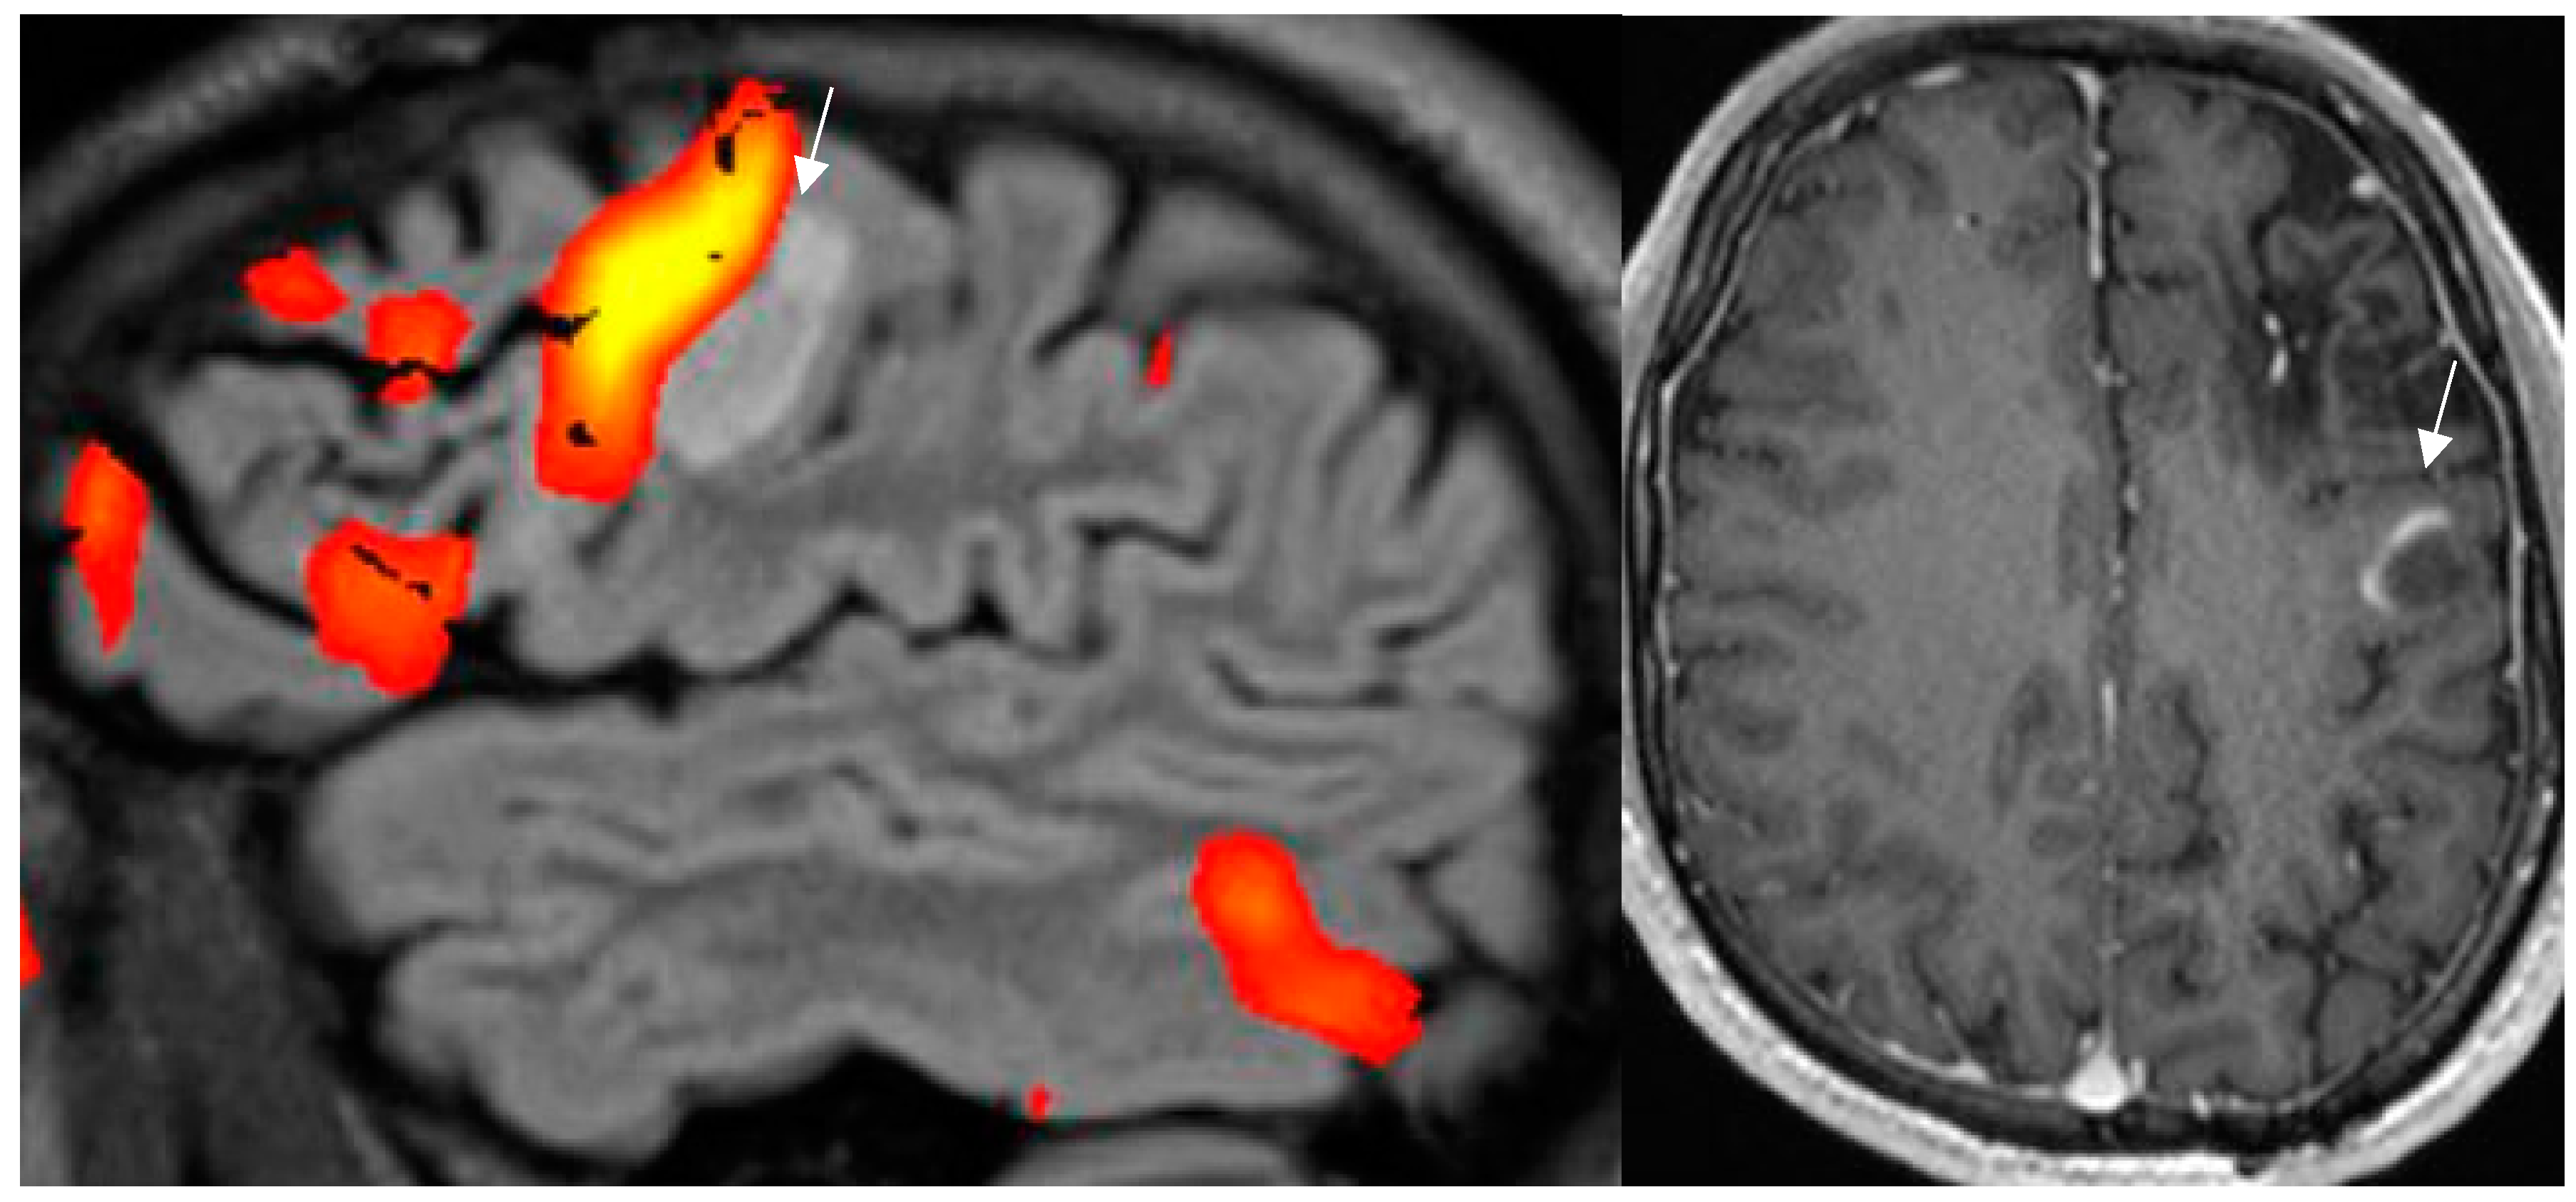

4.10. MR Perfusion Exploits Blood Flow to Identify Interictal Laterality of a Focus

4.11. Contrast Administration Is of Limited Gain with Respect to Lesion Detection But May Contribute to Characterization of an Abnormality